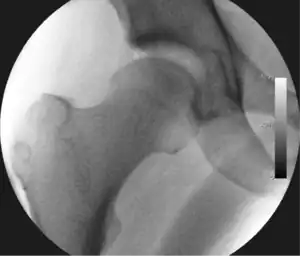

![]() Intraoperative fluoroscopic image during an arthroscopic resection of a cam lesion of the femur. The upper instrument is the arthroscope (viewing device), while the lower is the high-speed burr used for reshaping the bone. |

Cam-type femoroacetabular impingement

Cam impingement is created by the abnormal development of the femoral head-neck junction causing what has previously been described as a 'pistol-grip deformity'. This type of deformity is characterised by varying amounts of abnormal bone on the anterior and superior femoral neck at the head-neck junction (see fig. 6). The head-neck junction is at the base of the ball of the hip, where it joins the short neck, which in turn carries on downwards into the femur, or thighbone, itself. A bony protrusion or bump at the head-neck junction has been likened to a cam, an eccentric part of a rotating device. This leads to joint damage as a result of the non-spherical femoral head being forced into the acetabulum mainly with flexion and/or internal rotation. This may impart compression and shear forces to the articular cartilage, and may lead to labral tears and peeling away of the articular cartilage from the underlying bone, so-called cartilage delamination (see fig. 8).[9][10]

Standard arthroscopic treatment of symptomatic cam FAI involves debridement (resection) or repair of any labral [10] and chondral injuries [11] in the central compartment of the hip, and subsequent reshaping of the head-neck junction of the upper femur (osteochondroplasty) in the peripheral compartment [12][13] using high-speed motorised burrs that are similar in design to a dentist's drill (see fig. 9).